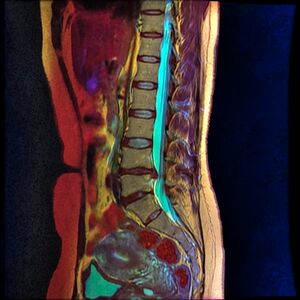

Desiccation of the L4-L5 and L5-S1 spinal discs are evident on color MRI as loss of blue color visible on these levels.